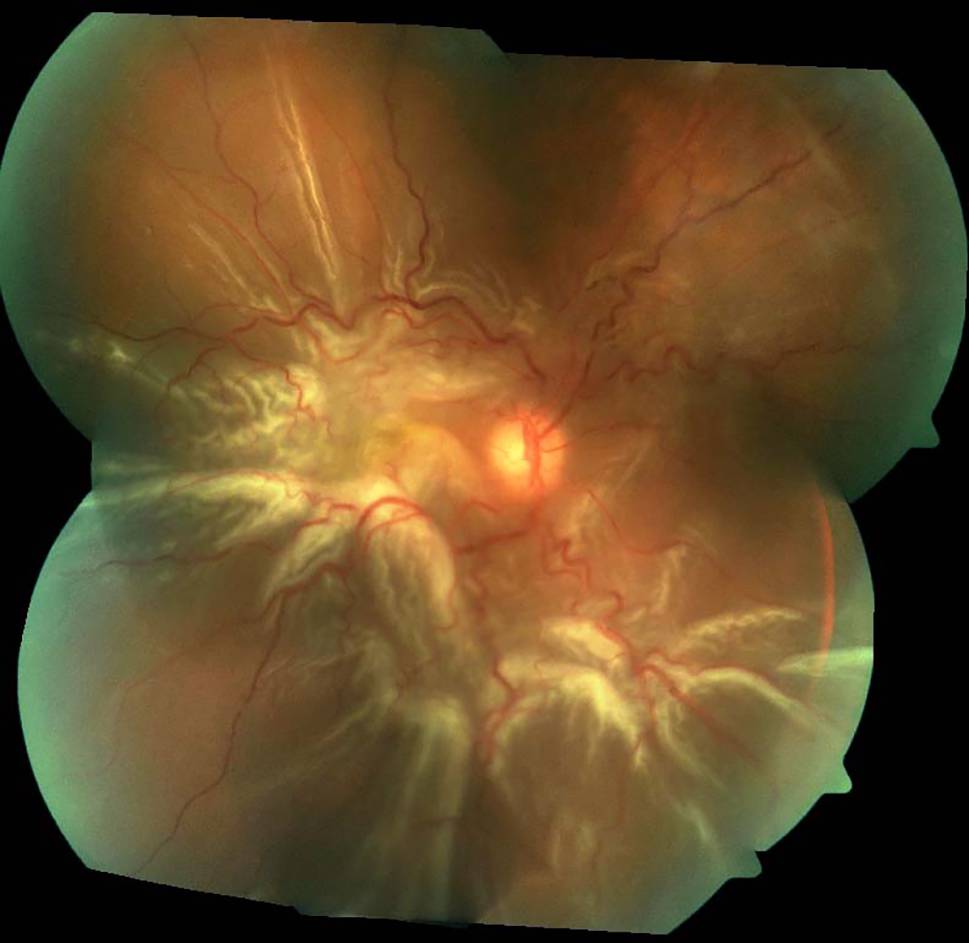

Fig. 3

Colour fundus photograph of the right eye demonstrating proliferative vitreoretinopathy grade C retinal detachment with retinal star folds

Proliferative vitreoretinopathy

The pathophysiology of proliferative vitreoretinopathy (PVR) has been extensively studied, with resultant formation of contractile proliferative cellular membranes on both the vitreous cavity and the retina [85]. Contraction of these membranes and intraretinal fibrosis can cause the retina to re-detach and fail to flatten. It is the most common cause of retinal detachment repair failure, with an incidence of 5–10% among all cases of RRD [86, 87]. Proliferative vitreoretinopathy grading was first recognised by The Retina Society Terminology Committee in 1983 and then updated in 1991 [86, 88, 89]. Grade A PVR was defined as the presence of vitreous haze and pigment clumps. Grade B PVR involves retinal wrinkling, rolled edges of the retinal break with retinal stiffness and vessel tortuosity. Grade C involves full-thickness retinal folds and/or subretinal bands and pathologic changes that can occur anteriorly, posteriorly or both. Grade C PVR was further differentiated into types 1–5, depending on the location of proliferation, type of contraction and extent in clock hours ([86, 89]; Fig. 3).